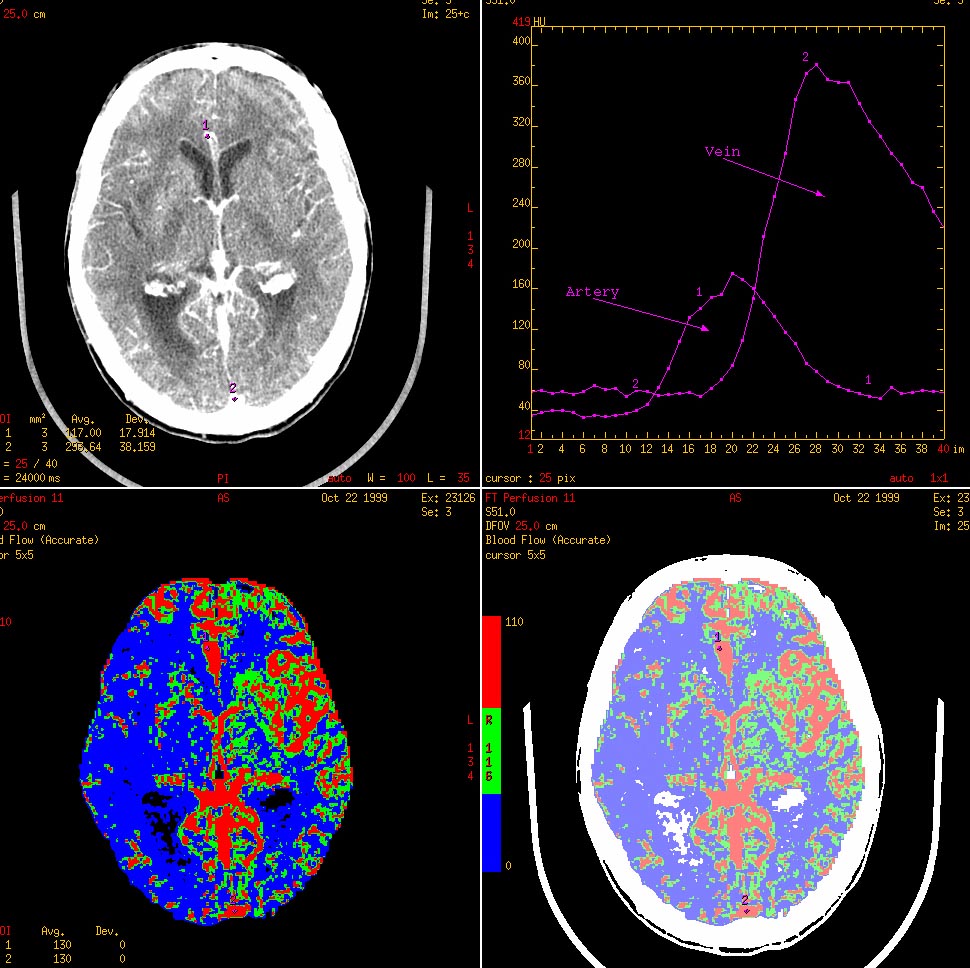

КТ стала одним из основных методов изучения перфузии головного мозга, что имеет большое значение при обследовании пациентов с острыми нарушениями мозгового кровообращения (Рис.2). МСКТ в сочетании со специальными методами трехмерной обработки изображений дает возможность получать изображения внутреннего просвета сосудов и состояния их и стенок как при эндоскопическом исследовании.